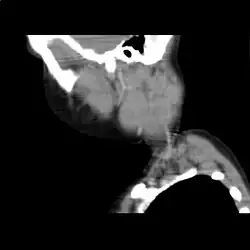

Computertomographie des Halses bei hochmalignem Non-Hodgkin-Lymphom der Halslymphknoten (rekonstruierter Sagittalschnitt).